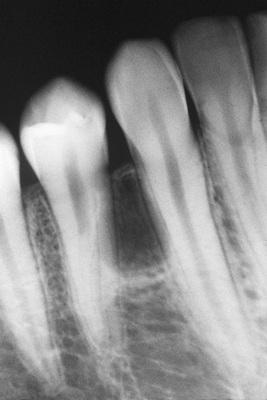

A unilocular radiolucent cyst involving the crown of an unerupted tooth, with the crown projecting into the cystic cavity.

dentigerous cyst, central type

A unilocular radiolucent cyst along the mesial root of the unerupted molar. This cyst exhibited mucous cell prosoplasia.

dentigerous cyst, lateral type